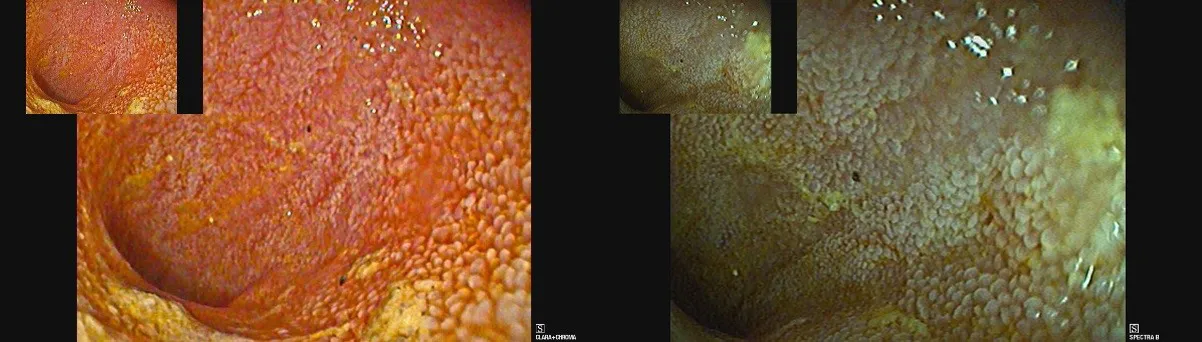

Endoscopical view of the inside of the small intestine: Left panel: normal view where the mucosa appears pink/ orange. Right panel: special \"narrow band imaging\" settings, where the mucosa and vessels appear pale green/ brown.

The second test is a type of imaging performed during normal gut endoscopy, which involves to switch from normal white light of the endoscopic camera to a more green looking light spectrum (a narrower range of light wavelengths), as this allows to see some features of the gut mucosa more clearly (for example blood vessels that cannot normally be seen are now seen as brown/ black). This is called narrow-band imaging (NBI) and has been used to increase detection rates of certain diseases in human endoscopy for a while already.